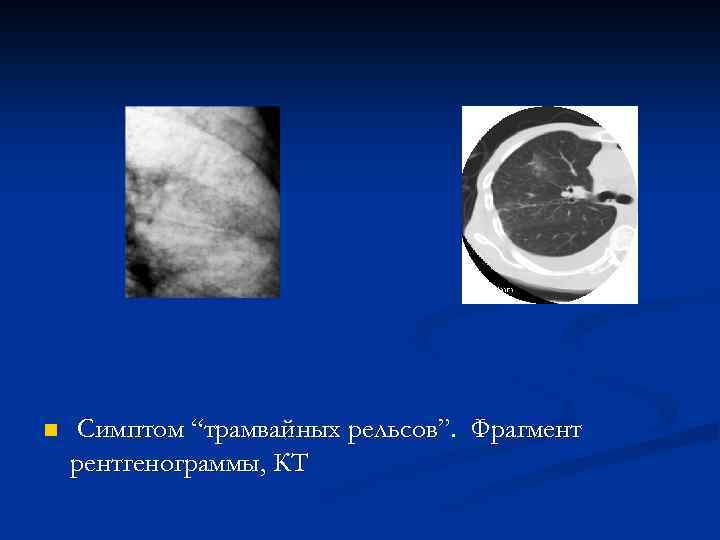

n Симптом “трамвайных рельсов”. Фрагмент рентгенограммы, КТ

n Симптом “трамвайных рельсов”. Компьютерная томограмма.